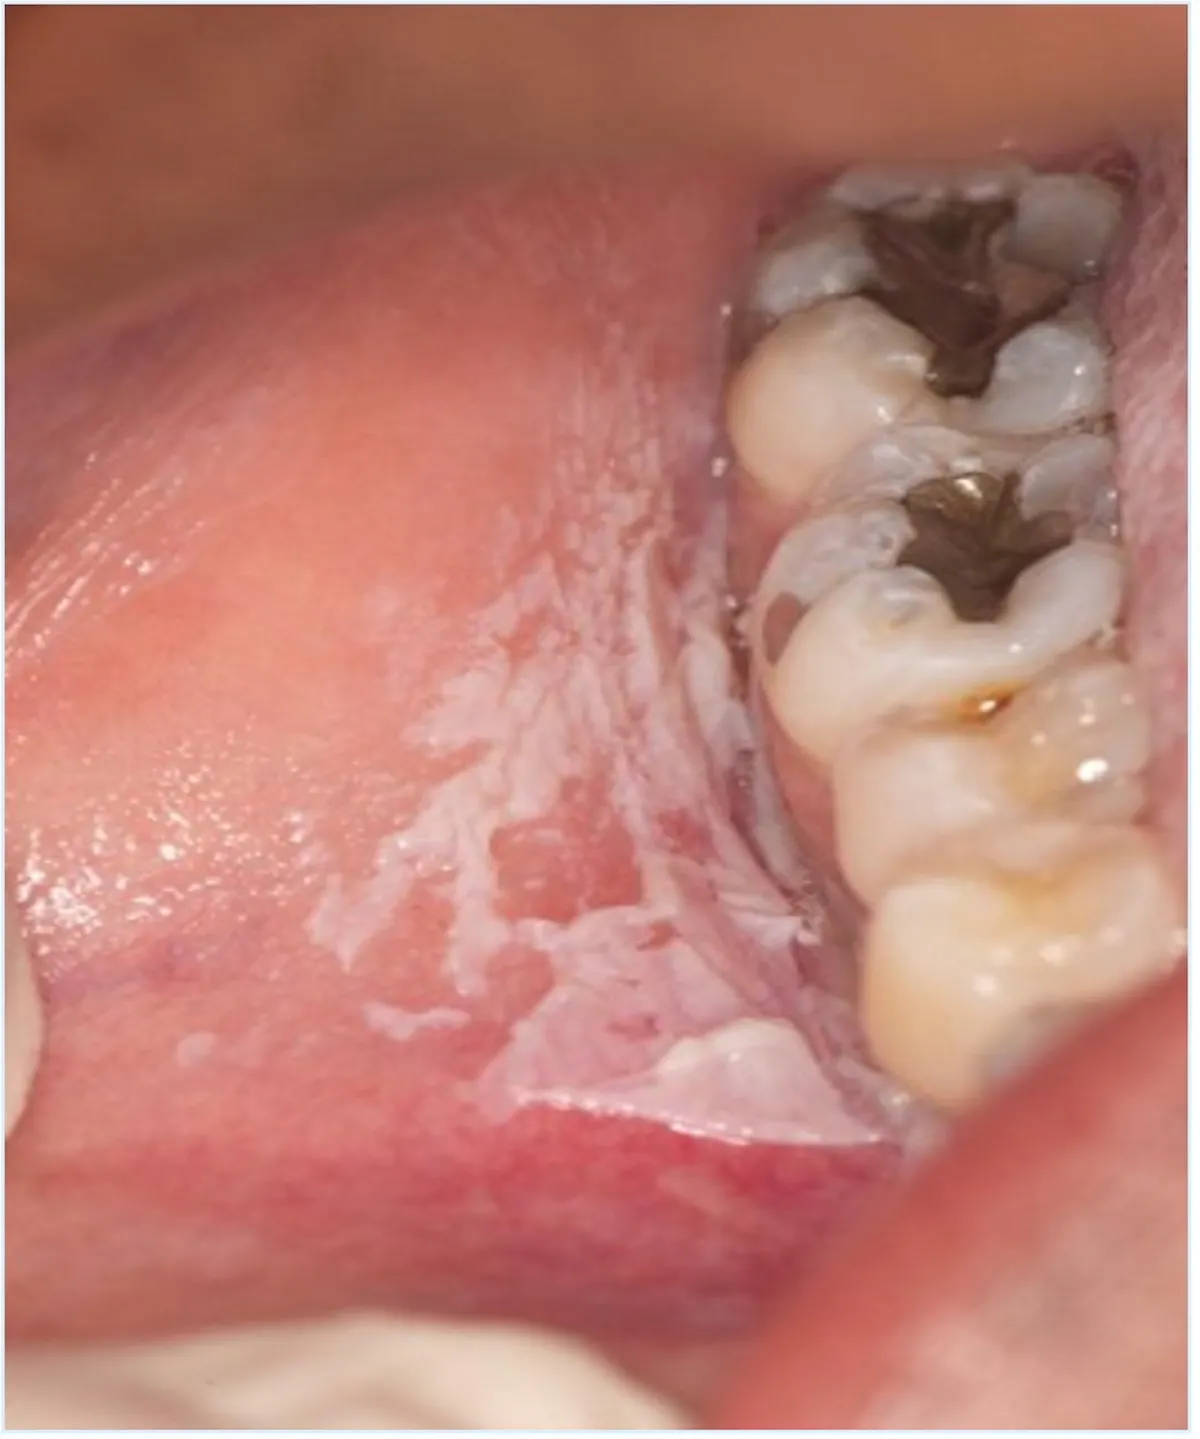

Figure 3 from Chemical burn from direct application of aspirin onto a Aspirin Burn In Mouth Treatment Aspirin, if left on the mucosa for an extended period, has a caustic effect. patients experiencing toothache may place an aspirin tablet adjacent to the affected tooth in an. treat these lesions with saline mouthwashes and topical application of diphenhydramine syrup. the oral ulceration was initially treated with systemic corticosteroids (betamethasone, 4 mg once a day for.. Aspirin Burn In Mouth Treatment.

Figure 1 from Aspirin induced intraoral burn A rare case report with Aspirin Burn In Mouth Treatment treatment is aimed at increasing secretions or moisturizing the mouth. Saliva substitutes, or artificial saliva, have the. aspirin tablets can be directly placed on the painful tooth and adjunct mucosa to relieve pain and avoid dental. most cases of chemical burns are encountered by aspirin, also known as acid burn, and its derivatives when sucked, applied as. Aspirin Burn In Mouth Treatment.